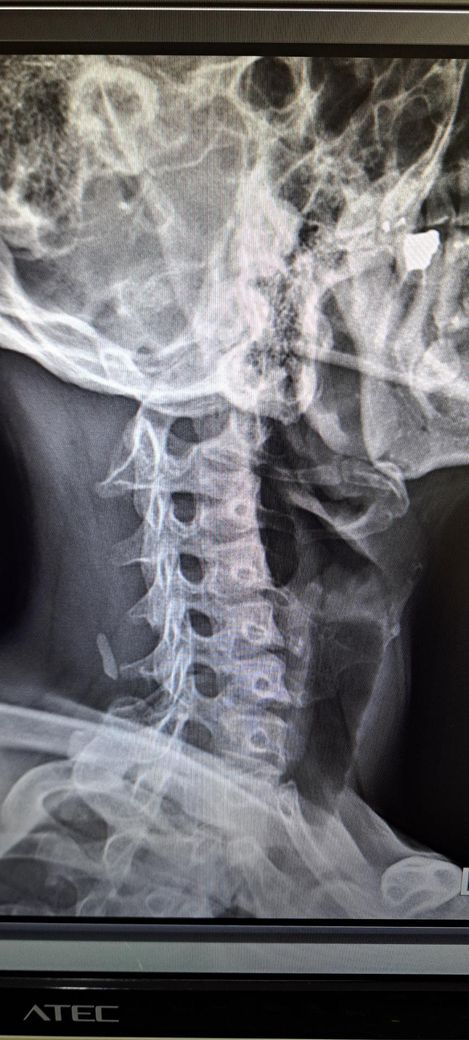

또한 일자목도 있다는데 심각한 정도인가요?

목은 일자목 경향은 있으나 심한 변형보다는 자세성 문제로 보이며 교정운동이 중요합니다.

또한 목은 일자목이 있으며 역C자 수준 까지는 아니라고 생각됩니다.

정면 사진상 골반의 좌우높이 차이가 관찰되며, 이는 대퇴골의 위치변화와 연관되어 보입니다. 측면 사진에서 요추의 곡선이 다소 꺾여 있는 양상이 보여 골반 전방경사 가능성이 큽니다. 정면 영상에서 척추가 일직선이 아니라 완만한 S자 형태로 휘어있는 측만 소견이 보입니다. 심각한 수준은 아니나 지속적인 관리가 필요한 상태입니다. 측면 사진상 경추의 커브를 보면 일자목 상태입니다. 골반이 높은쪽의 근육은 이완시키고, 낮은쪽과 약해진 둔근, 복근을 강화하는 운동이 필요합니다. 전방경사 완화를 위해 장요근 스트레칭과 프랭크 같은 코어 운동이 효과적입니다. 흉쇄유돌근 스트레칭과 더불어 등 근육을 강화하여 어깨를 펴는것이 급선무입니다.

보여주신 X-ray를 보면 우선 첫번째 사진에서 경추전만이 무너져서 일자목을 넘어 역 C자가 만들어진걸 볼 수 있습니다. 평소 고개를 앞으로 굽히지 않는 경추전만 자세 교정이 필요하겠으며 아래 영상 보시면서 자세를 교정해보시기 바랍니다. 아래 영상은 디스크에 대한 영상이지만 결국 교정해야할 자세는 같습니다.

x-ray 결과로 보아서는 경추C자 곡선이 반대로 되어 있어 일자목이 심해 보이며 골반 틀어짐과 척추측만증이 있는 것으로 보입니다.

신체 전반적으로 불균형과 척추 변형이 있기 때문에 경추부터 요추, 골반까지 전체적인 교정이 필요해 보입니다.